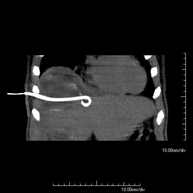

Consisteix en col·locar un catèter de drenatge sobre una col·lecció líquida localitzada a la cavitat abdominal, amb la intenció de buidar el màxim possible aquesta col·lecció. El pacient ha de mantenir el drenatge alguns dies, normalment fins que no sigui productiu. Sovint es realitza sota sedació, amb l'ajuda de l'equip d'anestèsia. Tot el procediment es realitza controlat per imatges obtingudes per Tomografia Computaritzada (TC) en diversos moments de la prova mitjançant l'ús de Fluoroscòpia –TC. Després de la prova, el pacient resta hospitalitzat. És necessari que porti les proves de coagulació abans de la prova.

It consists of placing a drainage catheter over a collection of fluid located in the abdominal cavity, with the intention of emptying as much of the collection as possible. The patient should keep the drain in place for a few days, usually until it is no longer productive. It is often performed under sedation with the help of an anaesthesia team. The entire procedure is monitored using images obtained by computed tomography (CT) at various stages of the test, using CT fluoroscopy. After the test, the patient remains hospitalised. Coagulation tests must be performed before the test.